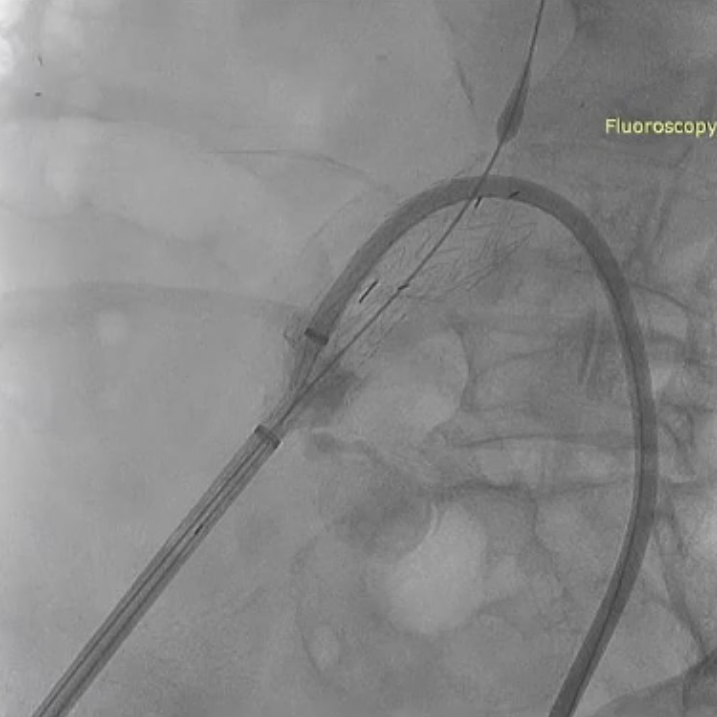

随后IBE主体就位,释放主体并翻山DSF鞘至短腿确认髂内情况,确认髂内健康锚定区情况及长度测量,释放髂内分支。对髂内支架狭窄处扩张,输送和释放第二枚髂内分支并手推造影确认通畅,IBE主体及各连接处后扩。

左侧髂内动脉超选与重建

右侧髂内动脉重建完成后,建立对侧翻山通路,再次确认主体位置及左侧髂内动脉情况。左侧髂内超选困难,经反复确认导丝配合导管超选真腔,手推造影确认髂内情况后释放远端VB,释放左侧髂内分支HGB并确认通畅情况。最后按常规EVAR置入腹主动脉支架主体,超选入主体短腿内对接IBE主体释放桥接喇叭腿。

左侧髂内分支HGB释放

手推造影确认通畅情况